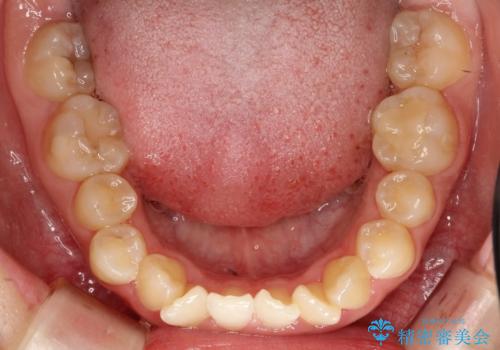

- 上下の前歯に激しい段差がある**重度の叢生(がたつき)**を主訴にご来院されました。精密検査の結果、歯をきれいに並べるためのスペースが圧倒的に不足していたため、上下左右の4番目の歯(第一小臼歯)を計4本抜歯する計画を立案しました。

本症例では、まず抜歯した大きなスペースを効率よく使い、歯の根元から大きく動かす必要があるため、初期段階にワイヤー矯正を採用。その後、細かな噛み合わせの調整や仕上げにインビザラインを使用する「ハイブリッドな矯正治療」で、期間の短縮と精度の高い仕上がりを目指しました。

ワイヤー矯正による先行治療: 最初のステージでは、ワイヤー装置を使用して抜歯したスペースへ歯を大きく移動させました。重度の叢生の場合、ワイヤーを用いることで歯のねじれや大きな移動をスピーディーに行うことができ、治療期間の短縮につながります。

治療の結果、重度のがたつきは跡形もなく解消され、抜歯したスペースもきれいに閉じました。ワイヤーによる「確実な移動」と、インビザラインによる「緻密な仕上げ」を組み合わせることで、審美性と機能性の両立を叶えた美しい歯並びを実現しました。